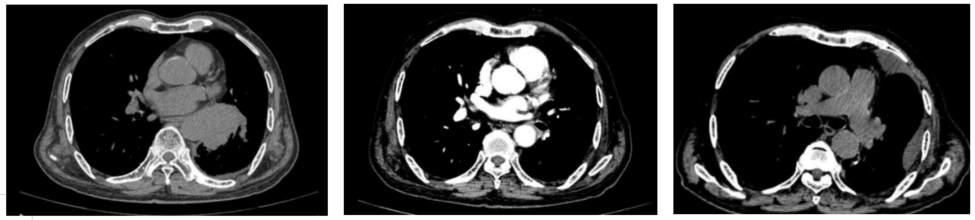

男性,75岁,2024-07-31诊断为cT4N0M0 IIIA期左下低分化肺腺癌,基因检测显示携带BRAF V600E突变,经筛选后2024-09-05入组启动“达拉非尼+曲美替尼”新辅助治疗,术前影像达PR,2025-07-22行VATS 辅助下左下肺叶切除+肺门纵隔淋巴结清扫+胸腔粘连松解术,术后病理达pCR,2025-08-01行“达拉非尼+曲美替尼”辅助治疗,截至目前术后4个月随访疗效评价仍未见复发。

影像学评估

ScreenShot_2025-12-09_163353_848.png

ScreenShot_2025-12-09_163424_322.png

图片1.png